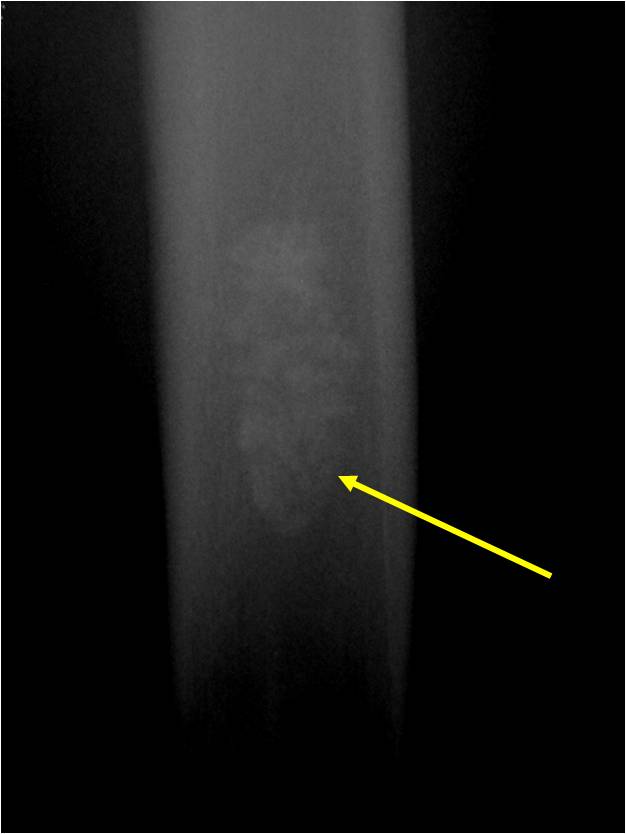

Plain X-Ray:

- Geographic lytic lesion

- Central often metaphyseal in long bones

- Can be eccentric also

- Expansile remodeling with thinned cortex

- Chondroid matrix with calcifications in majority of tumors

- Approximately 20% have limited or no calcifications

Ring and Arc Calcifications Minimal Endosteal Scalloping Cortex Intact No Soft Tissue Component No Periosteal Reaction

Ring and Arc Calcification No Endosteal Scalloping

Metaphyseal Tumor Heavy Calcifications Ring and Arc Pattern of Calcifications Minimal Endosteal Scalloping No Cortical Destruction No Periosteal Reaction No Cortical Destruction No Soft Tissue Component